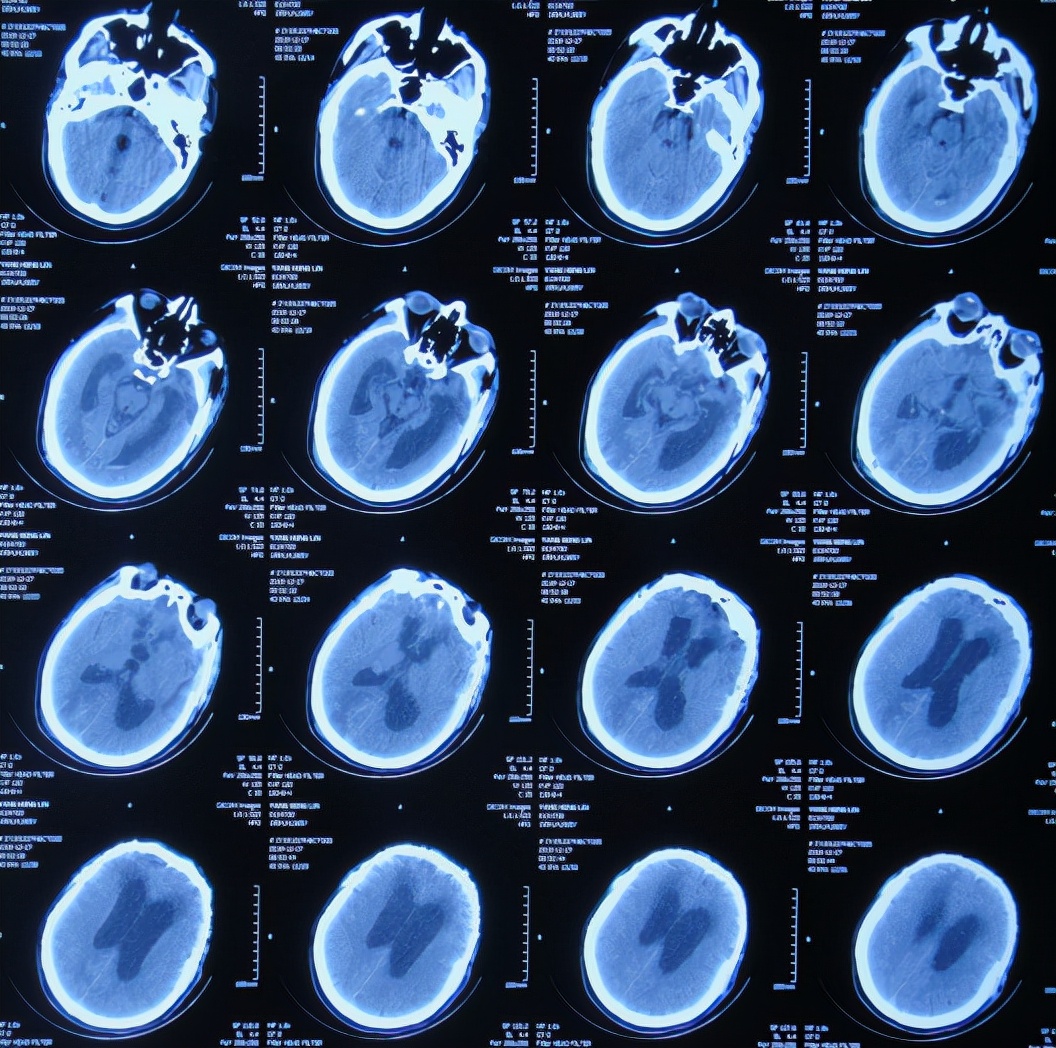

急诊进行了开颅去骨瓣血肿清除术,术后次日查头颅CT示去骨瓣术后( 图-2 )。

图-2: 2019年10月21日头颅CT

开颅术后第2天即2019年10月22日,仍昏迷,查头颅CT示积血未见减少( 图-3 ),给予腰椎穿刺术。

图-3: 2019年10月22日头颅CT

开颅术后第4天即2019年10月24日,查头颅CT示积血仍未明显减少( 图-4 )。

图-4: 2019年10月24日头颅CT